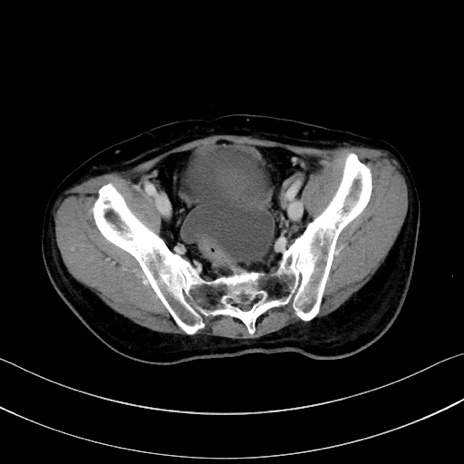

症例28(横断像)

【症例】60歳代男性

【主訴】嘔吐

【現病歴】胃癌にて胃全摘後。食思不振が悪化し、夜中に嘔吐することがある。

【既往歴】胃癌、胃全摘、脾摘、胆摘後

【データ】WBC 5900、CRP 10.56